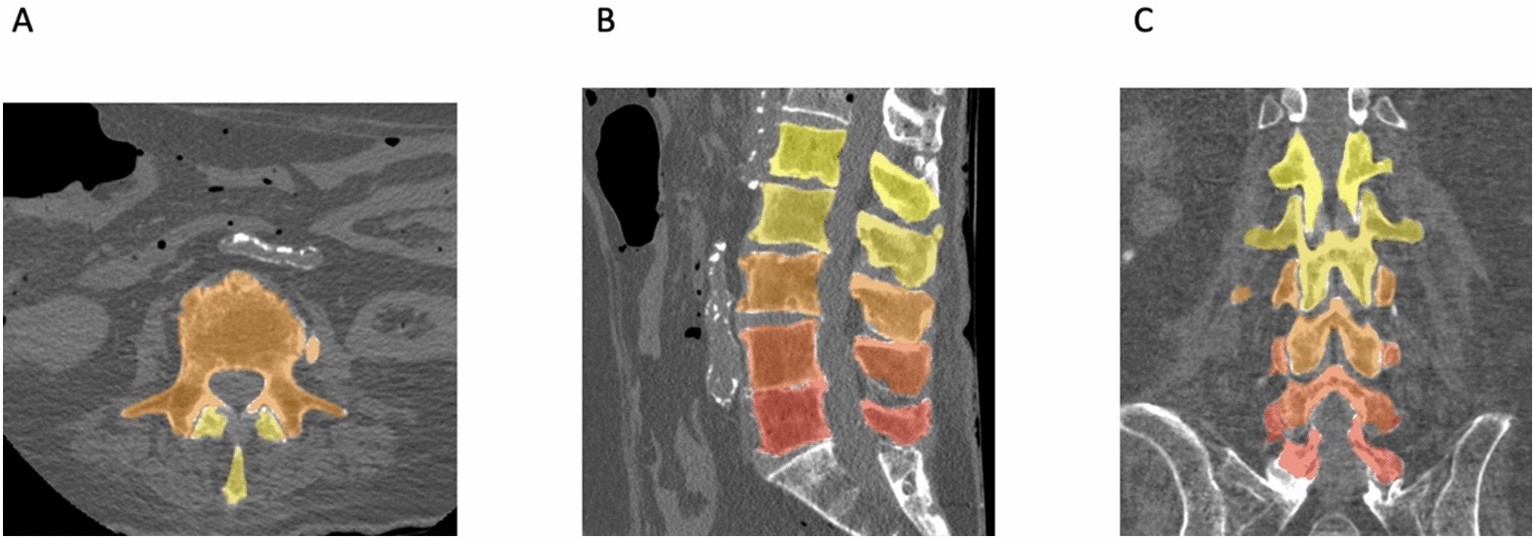

Deep Learning Segmentation of Lumbar Vertebrae. Volumetric segmentation of lumbar vertebrae shown in axial (A), sagittal (B) and coronal (C) views. L1 to L5 vertebrae were assigned with a scalar color from yellow to red.